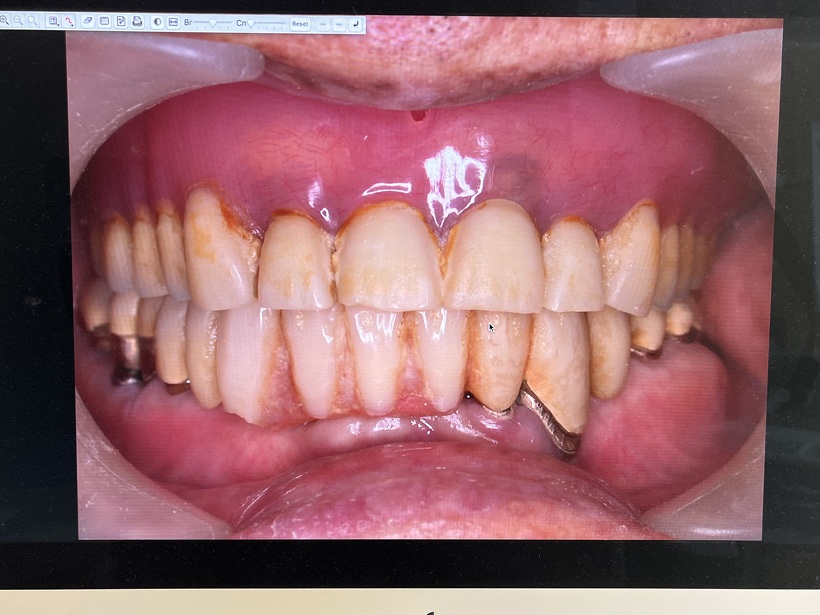

初診時 虫歯・歯周病・清掃不良

治療の結果上下で10本が残りました。上顎は2本の歯を総義歯の中に組み込みました。下顎のコーヌスブリッジ義歯 8本の支台歯(実際は7本ですが右下6番は根を2つに分割して使用しています)で14本の歯を作りました。